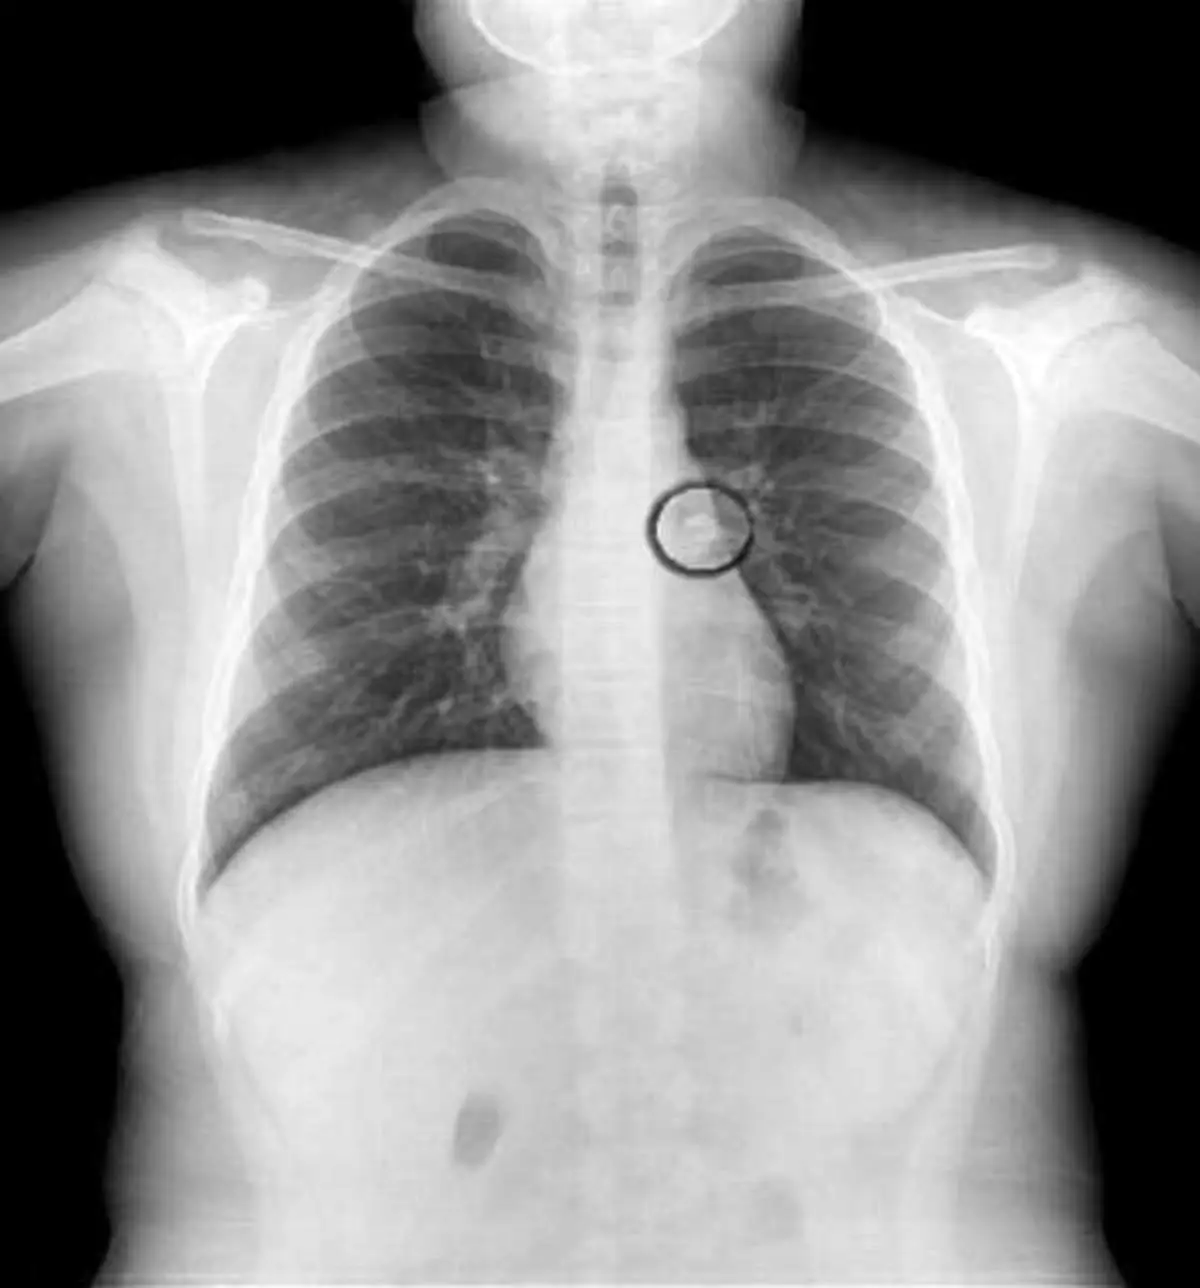

پزشک برای تشخبص دقیق و تبدیل شکش به یقین پیش از بازگو کردن حدسش عکسبرداری را تجویز کرد تا با توجه به نتیجه عکسبرداری علت را دقیق تر تشخیص دهد ؛ نتیجه همانی شد که پزشک حدس میزد و دندان ناپدید شده داخل ریه ی کودک دیده شد.

پزشک معالج این دختر میگوید :در بررسی های عملکرد ریه ها متوجه شدم که ریه ی سمت چپ او به صورت طبیعی کار نمیکند بنابراین فورا بعد از عکسبرداری برای خارج کردن دندان از ریه اقدام شد و با نوعی لوله موفق به این کار شیدم و کودک را از خطر نجات دادیم.